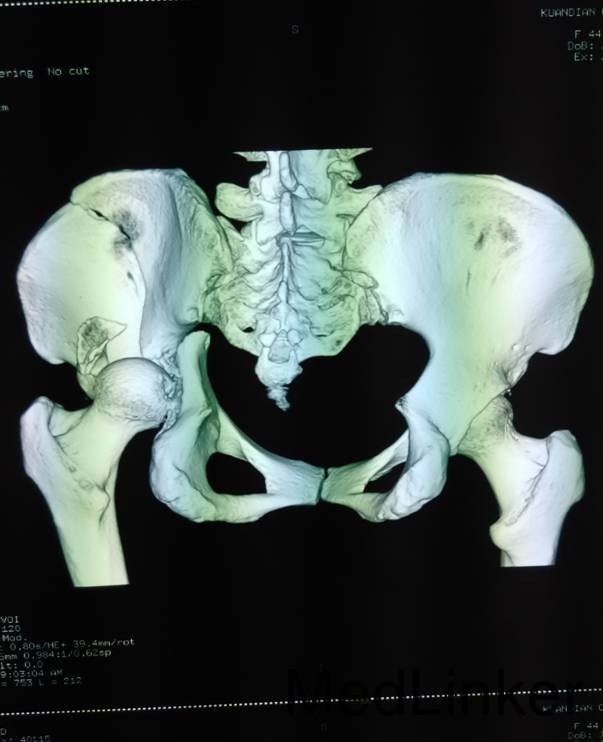

主诉:车祸外伤后左髋部疼痛伴活动受限4天 患者于2014年6月12日早6点左右被皮卡车撞伤,伤后患者出现一过性昏迷,被急诊送往当地医院,行DR及CT检查后,诊断为:左髋臼骨折,于当地医院骨科行骨牵引、抗炎补液等对症治疗后,现为求进一步治疗转入我科,患者病来无头晕头痛,无恶心呕吐,已排气排便.

患者左下肢股骨髁上骨牵引中,左髋部肿胀,臀部可见淤血瘀斑,骨盆分离挤压试验(+),左大腿肿胀,左下肢无明显短缩,纵向叩击痛(+),左下肢小腿外侧及足背麻木感,足背伸肌力正常,双足趾可活动,双侧足背动脉可触及搏动

入院后请神经外科会诊,请麻醉科会诊评估手术风险,查无明显手术禁忌症后,全麻下行左髋臼骨折切开复位内内固定术,术后留置引流,术后3天拔除引流管,切口换药无红肿渗出,术后4天转入当地医院继续治疗。

患者左髋臼骨折,髋臼骨折出血量大,应用自体血回输继续。术中注意血管及神经的副损伤。